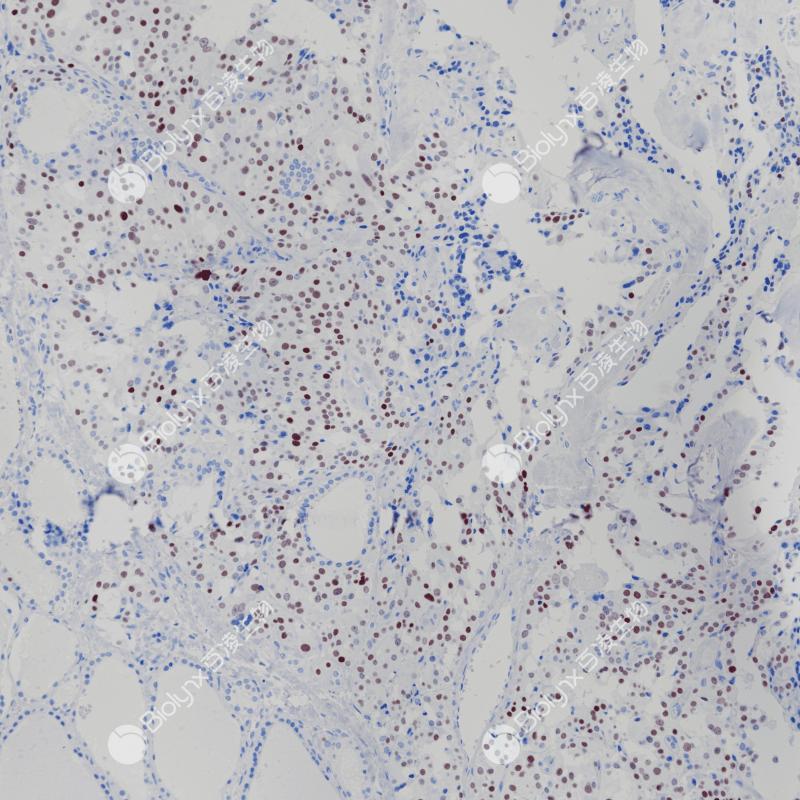

小细胞神经内分泌癌INSM1(BP6240)染色

甲状腺髓样癌INSM-1(BP6240)染色

INSM-1

重组兔单克隆抗体

胰岛素瘤相关蛋白1 (INSM-1),又称锌指蛋白IA-1,是一种发育调节的锌指转录因子。它定位于细胞核,并在经历神经内分泌分化的胚胎组织中表达。它在神经内分泌发育中起重要作用,是胰腺内分泌细胞正常分化所必需的。抑制INSM-1可减少胰高血糖素和胰岛素阳性细胞的形成。INSM-1在正常成人组织中不表达,但在神经内分泌肿瘤中高表达。INSM-1主要用于神经内分泌肿瘤的临床诊断。

阳性对照

甲状腺髓样癌

亚细胞定位

细胞核